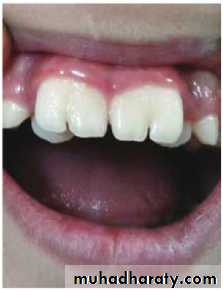

3- Anomalies of Tooth Shape

a.Most frequent “Peg Lateral” which leads to excessivespacing.